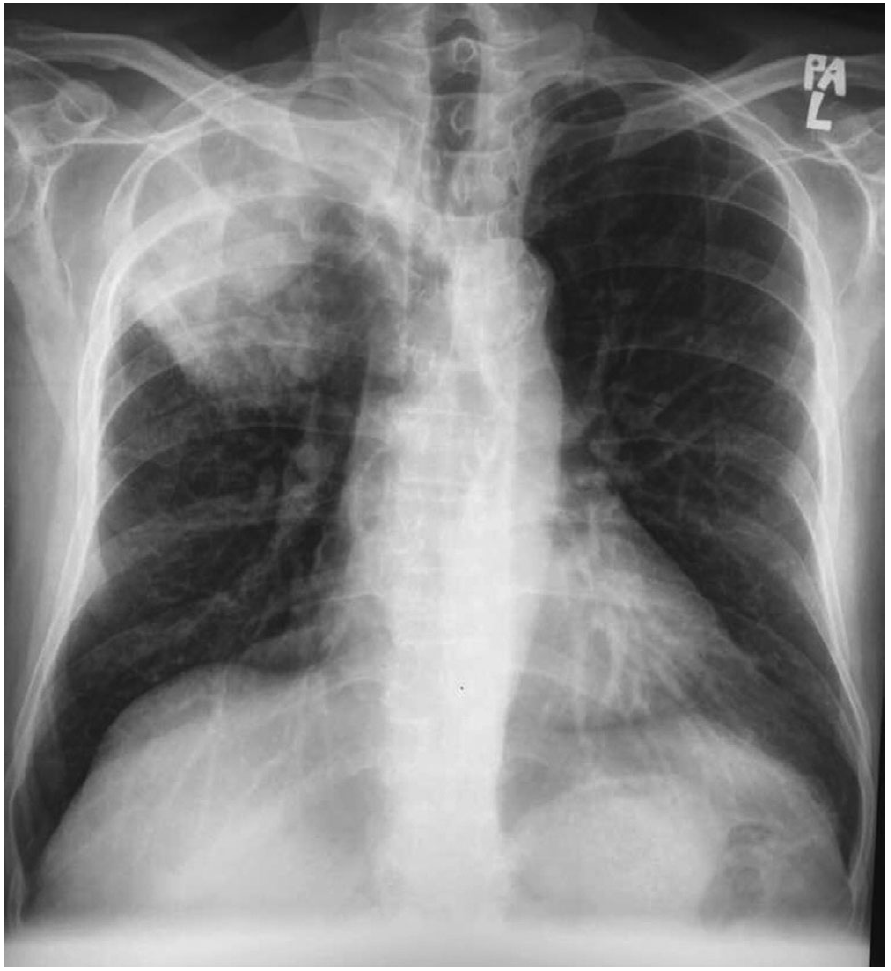

・レントゲンでは右上肺野に腫瘤を認めた